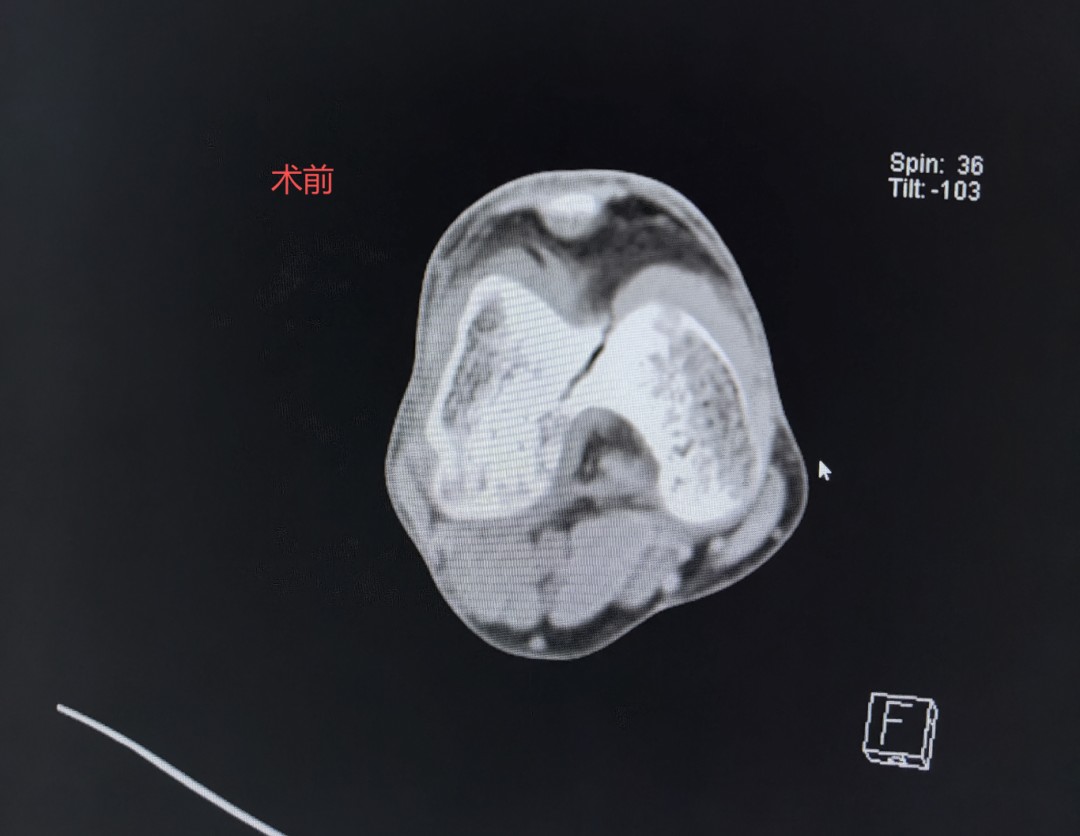

秋意初显,阳光和煦。9月20日骨二科医生办公室迎来一位熟悉的“家人”这位刚出院一个月的梅先生。他扶拐步履稳健,笑容满面,与入院时因车祸受伤平车推入院时判若两人。他此行的目的,一是回来复查,二是要亲手将一封情真意切的感谢信交到我们医务人员手中,以此表达对骨二科全体医护人员最诚挚的谢意。 时间回溯到2025年08月06日, 梅先生上班刚到单位门口车祸不慎致“右股骨髁间骨折、右膝半月板损伤”同事即送急诊后收治入我科,这次意外损伤不仅给梅先生不管是生活上还是愈合恢复都是一种困扰,伤筋动骨100天对一个家庭生活的支柱躺下来带来的困扰与焦虑也是不想而知,这175高的中年男子被这意外变得六神无主快崩溃了。 得知梅先生的意外和焦虑,骨二科罗永立主任带领团队迅速行动。马上制定精准的手术方案,于8月9日为梅先生行:右股骨髁间骨折切开复位内固定术 三分医治七分护理,徐凌峰护长带领护理团队秉承“以患者为中心”针对梅先生制定优质服务理念,从术后无痛管理、到早期快速康复功能锻炼指导,每一个环节都凝聚着我们的专业水平与人文关怀。在医、护、患三方的共同努力下,梅先生恢复神速,根据梅先生的情况术后第一天可以摇高床头坐起来,第二天可以扶床下地站,第三天扶拐下地活动。术后复查照片结果骨折对位良好,住院仅用了13天。梅先生就可以出院回家休养,这么快速可以回家?可以扶拐下地?再不是伤筋动骨100天的长期卧床等康复。家人同事与邻居看见梅先生从受伤到回家到可以下地活动,简单的生活能自理。真的让梅先生与家人象梦境一样。难以想象,便事件告诉他们这就是我们同江医院的精湛医术及优质护理。 当梅先生与古医生约好一个月要回院复查时,就带上出院后就写好的感谢信一起送到古医生手里,看见他扶拐稳健的步伐和灿烂的笑容。一封感纸短情长,字里行间充满感激的簿张却是对骨二科团队医术医德的赞誉和对护理工作的深切感激。这封信,不仅是对我们过往工作的肯定,更是鞭策我们不断前行的动力。 梅先生短短康复之旅,就是骨二科团队践行“敬佑生命、救死扶伤、甘于奉献、大爱无疆”职业精神的一个缩影。精湛的医术是根,优质的护理是叶,而患者的信任与康复,则是我们共同培育出的最甜美的果实。未来将继续用专业、爱心和担当,为每一位患者的健康保驾护航,书写更多温暖生命的奇迹! 图:患者感谢信